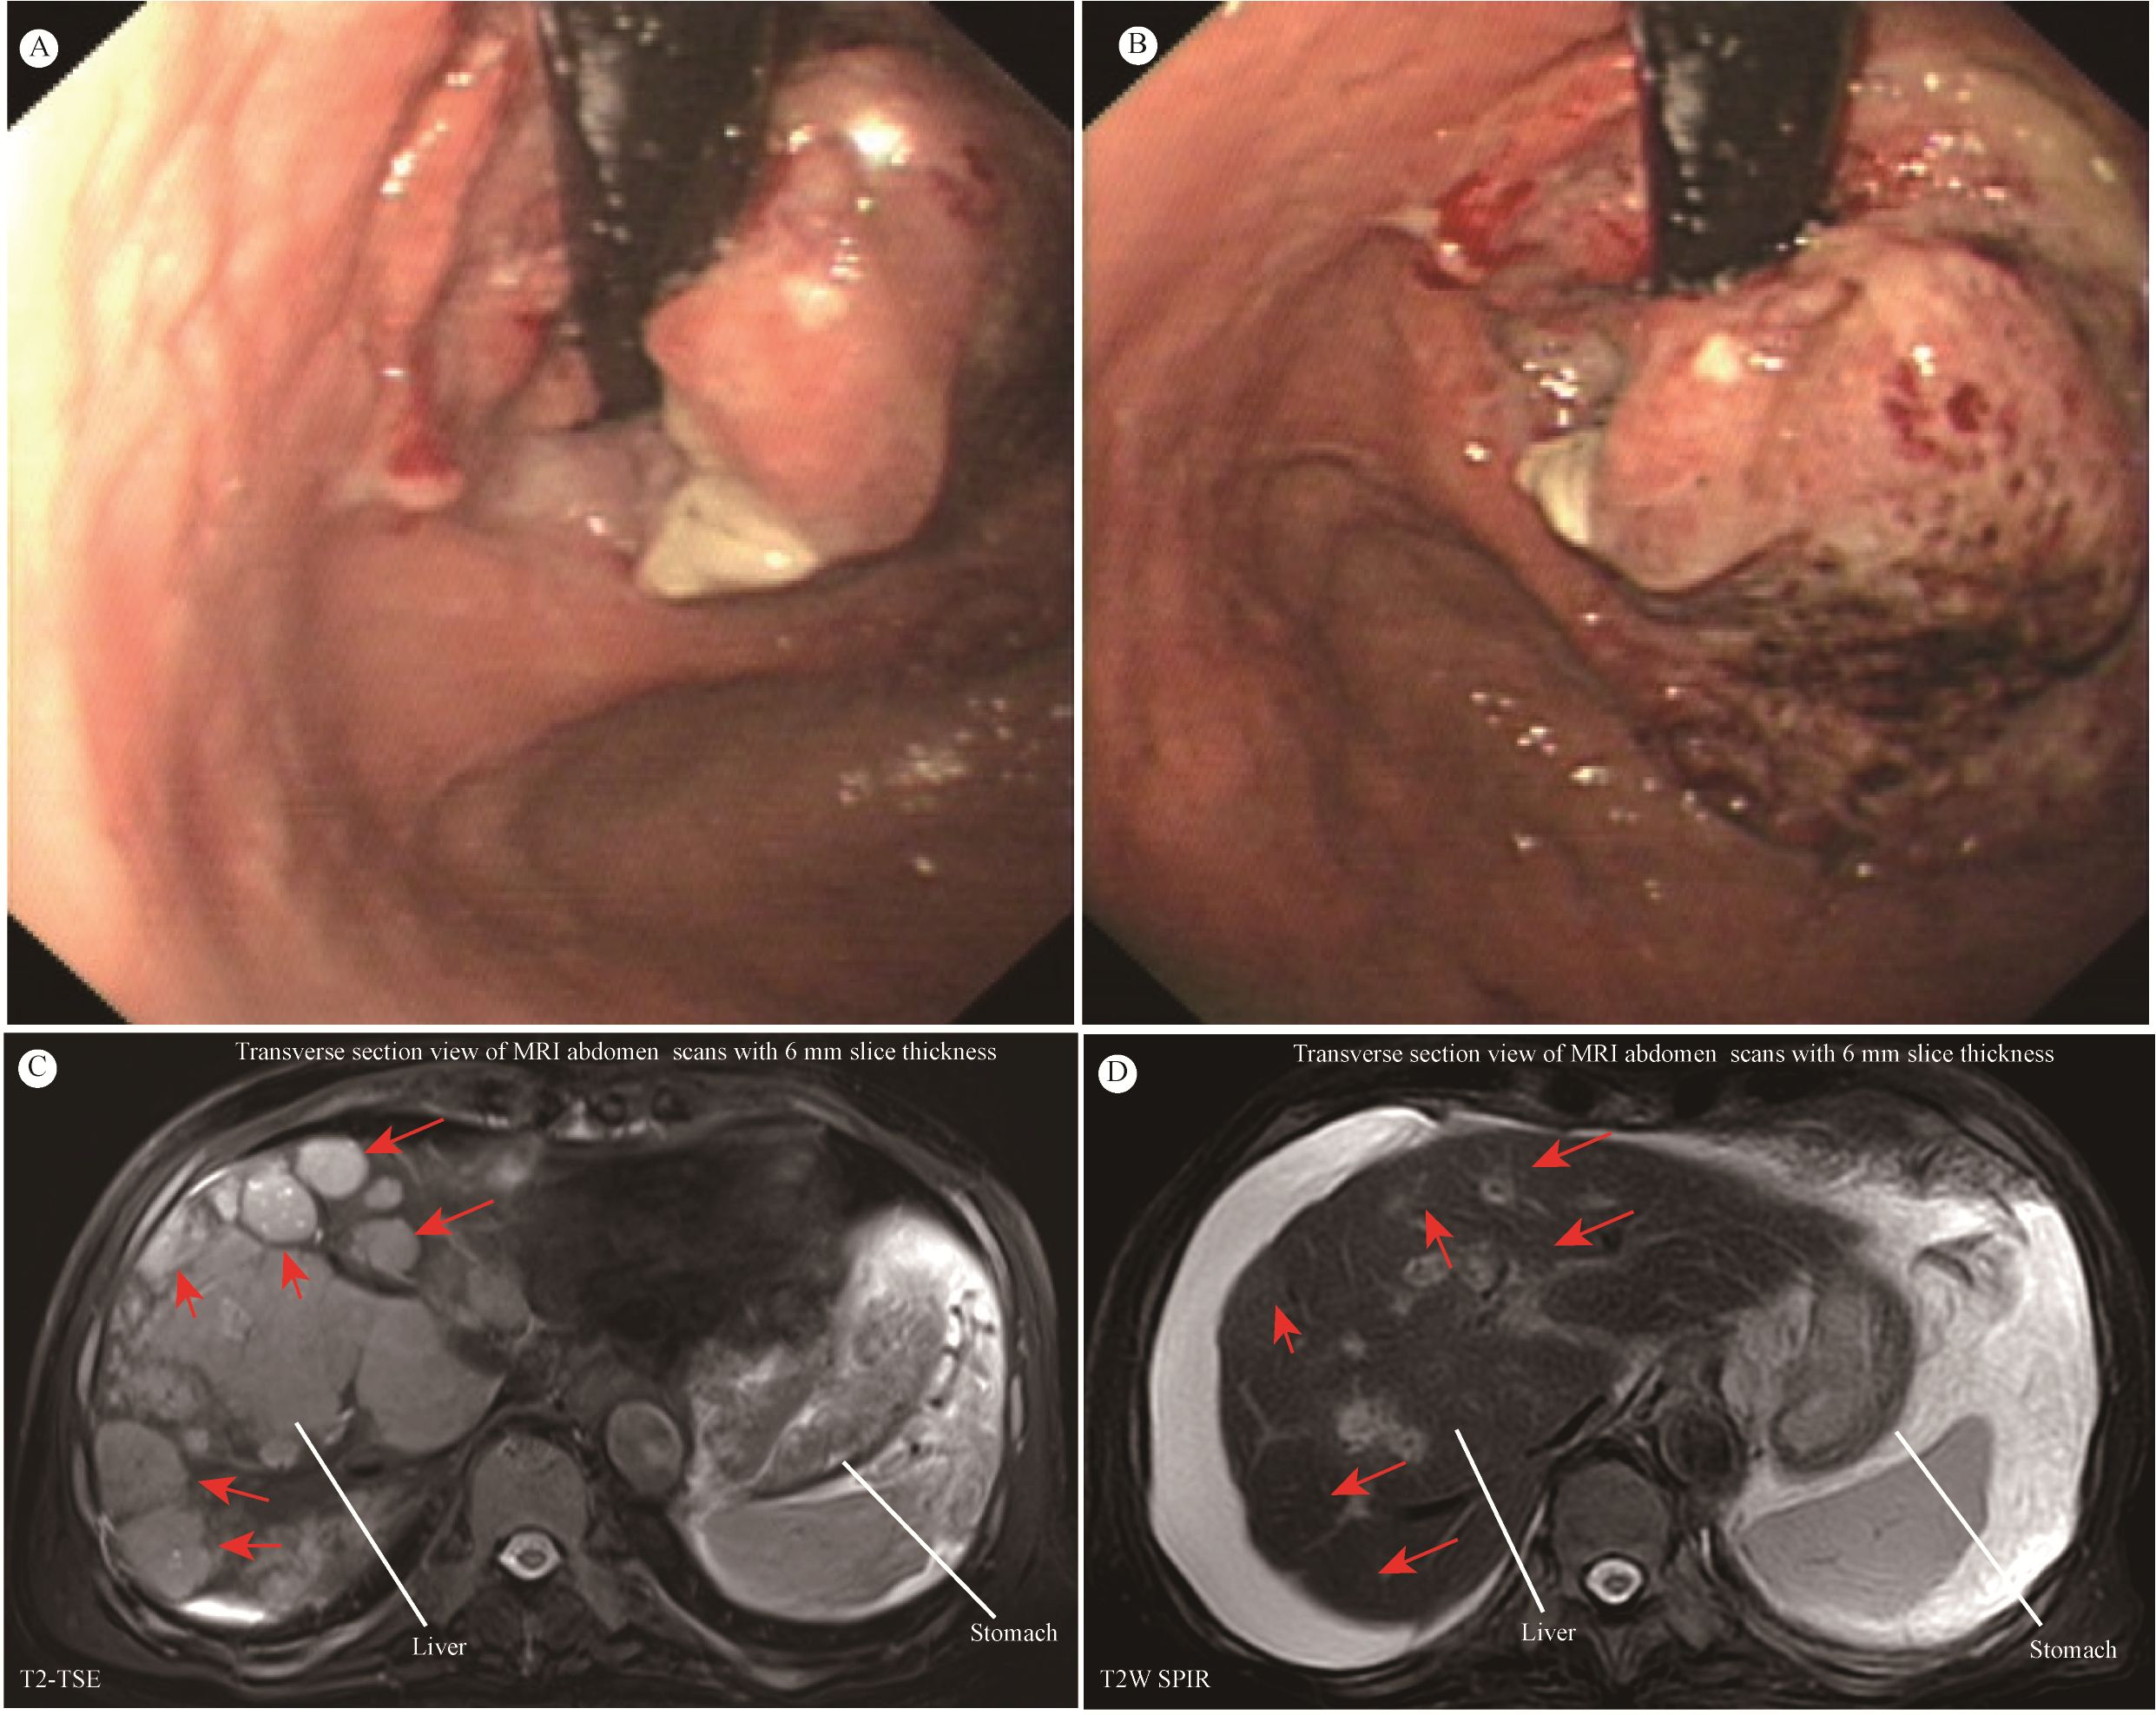

The patient, an 81-year-old male, underwent gastroscopy on April 7, 2024, which showed an irregular tumor on the lesser curvature and posterior wall of the gastric fundus. The tumor occupied about one-third of the gastric fundus area, presenting with ulceration, hardening, and active bleeding (Figures 1A, B). Enhanced abdominal MRI showed thickening of the gastric wall and multiple hepatic masses (Figure 1C). The pathology of the gastric biopsy revealed atypical cell infiltration, indicating a malignant tumor with two components: one part was moderately differentiated adenocarcinoma, while the other component exhibited a solid pattern of poorly differentiated carcinoma with strong neuroendocrine marker expression, suggesting large cell neuroendocrine carcinoma. Immunohistochemistry results were as follows: Adenocarcinoma component: CK8/18(+), CK7(+), Syn(-), EMA(+), Hepatocyte(-), Ki-67(40%+), Her2(1+), MLH1(+), PMS2(+), MSH2(+), MSH6(+), P53(80%+, mutated); Poorly differentiated carcinoma component: CK8/18(+), CK7(-), Syn(strong+), EMA(-), Hepatocyte(-), Ki-67(50%+), Her2(1+), MLH1(+), PMS2(+), MSH2(+), MSH6(+), P53(80%+, mutated); PD-L1(BP6099, TC score: 5%+). The diagnosis was stage IV gastric cancer with multiple hepatic metastases. Considering the patient’s advanced age, history of diabetes, coronary artery disease, chronic kidney disease, and poor liver and kidney function, nivolumab (240 mg q2w) monotherapy was initiated on April 9, 2024. After more than four months of monotherapy with nivolumab, contrast-enhanced MRI imaging demonstrates significant interval regression of multiple hepatic metastases and a substantial reduction in portal vein thrombus burden compared with prior examinations. Improved visualization of the middle and left hepatic veins is noted. The gastric wall exhibits mild thickening, which represents a mild improvement relative to previous findings. Furthermore, the mass at the gastric fundus demonstrates an interval reduction in size (Figure 1D).

Gastrointestinal endoscopy and MRI images are shown. Panel A shows an endoscopic view of a gastrointestinal lesion, which occupies approximately one-third of the gastric fundus area and is accompanied by ulceration, induration, and active bleeding. Panel B provides a closer view of the same lesion, revealing ulcerative changes. Panels C display transverse abdominal MRI scans, highlighting the gastric cancer and multiple hepatic metastatic lesions; red arrows indicate potential abnormal regions. Panel D demonstrates significant interval regression of multiple hepatic metastases and a substantial reduction in portal vein thrombus burden compared with previous examinations.

Figure 1. (A, B) Giant space-occupying lesion at the gastric fundus. (C, D) MRI of the abdomen. Contrast-enhanced MRI of the abdomen showed that the size and number of multiple liver metastatic tumor lesions have notably shrunk after more than four months of monotherapy with nivolumab (red arrow).